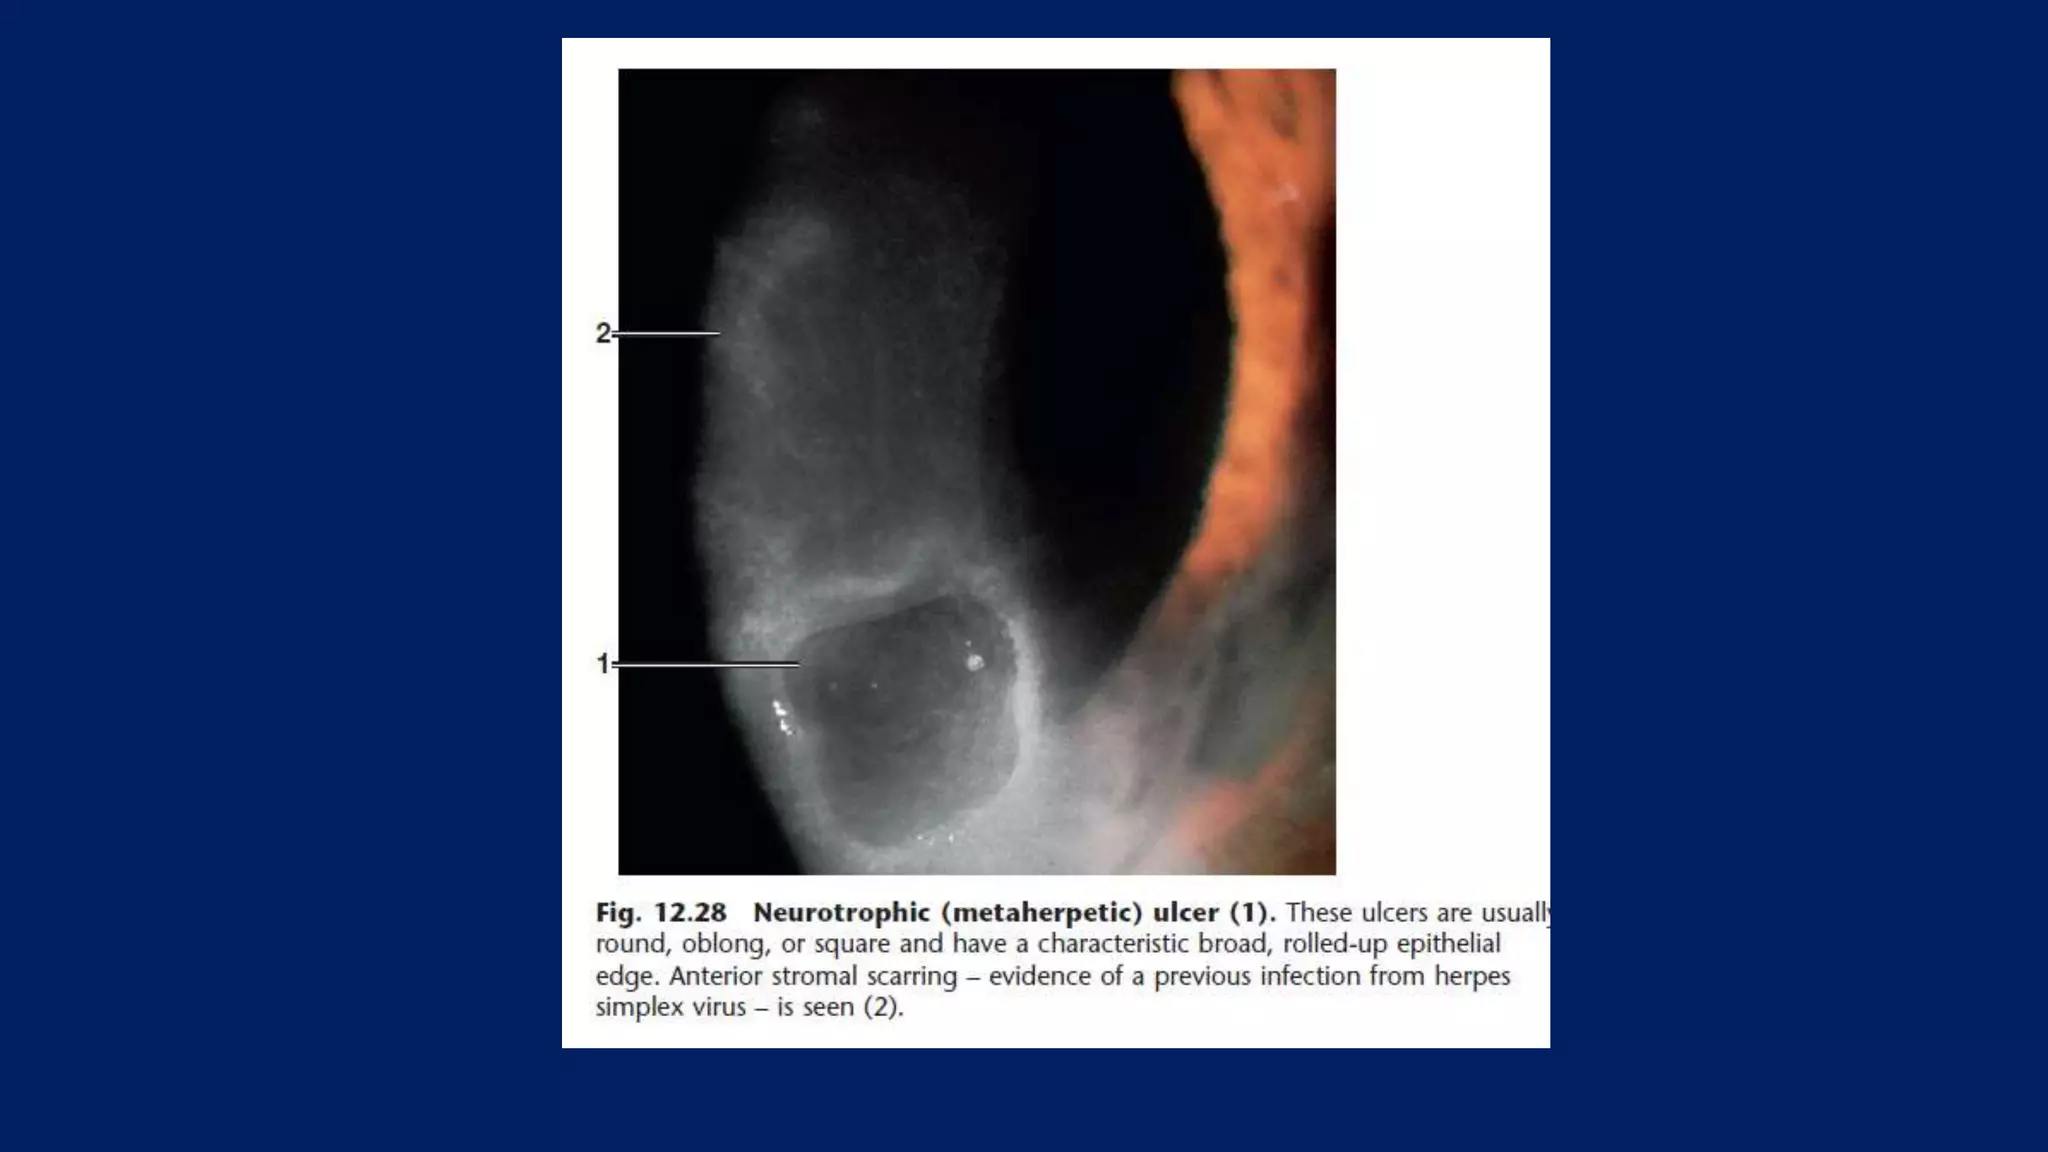

Herpes simplex keratitis with a large

geographic ulcer. These ulcers take

longer to heal than dendritic ulcers

Anterior

stromal scars.

“Footprints” in a

pattern of

herpetic

ulceration

indicate

previous

infection